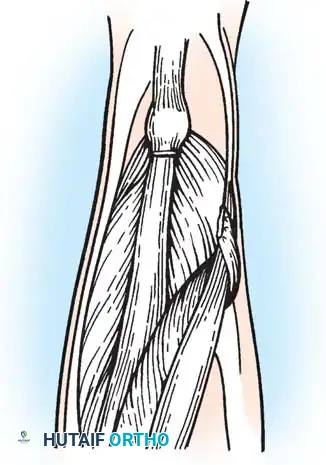

- Next, expose the semitendinosus tendon. Divide the distal portion of the tendon obliquely up to its muscle fibers. Depending on the severity of the contracture, incise the tendon transversely or perform a formal Z-plasty.

- Extend the knee and flex the hip simultaneously. The sectioned tendinous portion of the semimembranosus will slide smoothly over the intact muscle belly, achieving the desired lengthening.

Closure:

* Perform a similar dynamic lengthening maneuver by flexing the hip and extending the knee to ensure the lateral structures slide appropriately.

* Close all individual tendon sheaths meticulously with absorbable suture.

* Do not close the deep fascia. Leaving the deep fascia open prevents postoperative compartment syndrome and allows for the expanded volume of the sliding muscle bellies.

Separate meticulous closure of each tendon sheath; deep fascia is not sutured.

Fig. 30-25 Fractional lengthening of hamstrings overview. A, Skin incision and incision in deep fascia over back of knee. B, Incisions in semimembranosus. C, Incisions in biceps femoris. D, Tendon sheaths of biceps femoris and semimembranosus are sutured before wound closure.